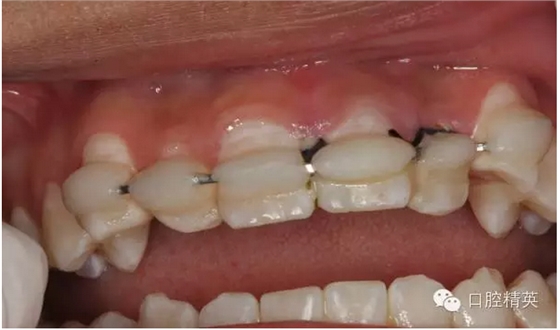

圖15.縫合初固定21

圖16.縫合初固定完畢

圖17.正確復(fù)位21.臨時(shí)光固化粘結(jié)

圖20.光固化樹(shù)脂+唇弓夾板固定

圖 21.修整粘結(jié)的樹(shù)脂形態(tài)

圖22.拋光樹(shù)脂

圖1.一周后復(fù)診拆線、唇側(cè)齦乳頭水腫。

圖3.拆線后唇側(cè)觀,牙齦乳頭輕度水腫